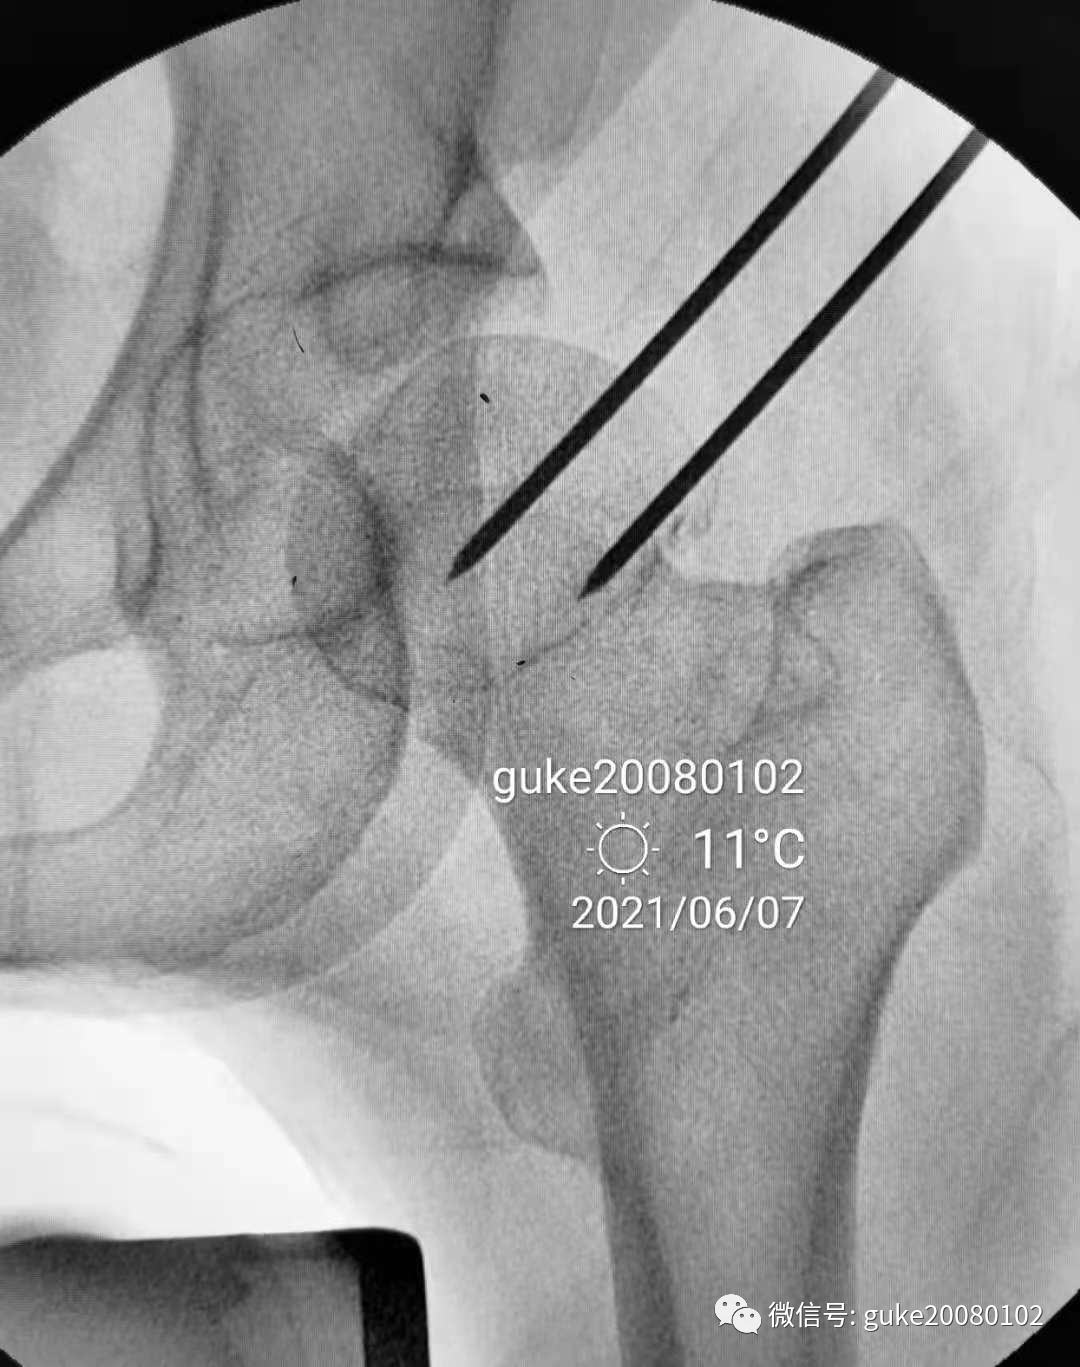

- 在大转子顶点近端5厘米处,经皮向股骨头上方插入直径2.0mm克氏针两枚,敲击克氏针至骨质,撬拨头颈骨折块复位。

- 撬拨力量偏小,骨折复位不足。再插入一枚2.5mm克氏针,接力撬拨,骨折复位。

1.正侧位观察骨折复位,骨小梁走形恢复。崁插骨折复位。